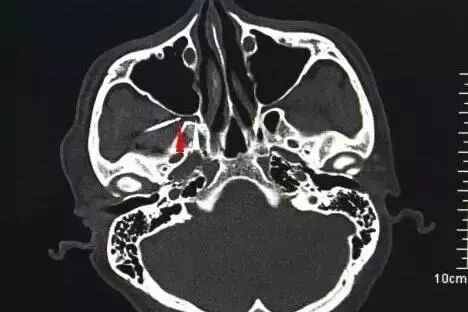

接诊的医生发现,小王的头痛是典型的“冰淇淋头痛”,学名又叫“蝶腭神经节神经痛”,和一次性进食大量冰冷食物有关。

医生介绍,“冰冷食物进食过量,上颚就会被迅速冷却,而上颚后部正好有一个神经中枢,这时,神经中枢的神经群会向大脑发送信号,以改变体温。”当冷食吃得太多时,这些神经群就会被过度刺激,向大脑发送错误的信号,导致大脑动脉痉挛,就像脑子被“冻”住了一样,血流猛地冲击痛觉神经末梢,这时人会感觉在额头中部或太阳穴附近剧烈疼痛,有的人还可能恶心呕吐。

简单点说,冰食吞得太快或是一口吞得太多,最容易引起这个症状。而等到上颚温度恢复正常后大脑就会“解冻”,头疼也随之解除,但有的患者症状明显。